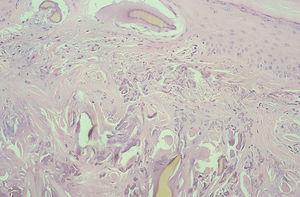

Se tomó, una biopsia de la cara lateral de uno de los índices afectados, y se observó una epidermis discretamente hiperqueratósica y acantósica. En la dermis superficial había una importante elastosis asociada a depósitos de material acelular de color ocre rodeado de una degeneración basófila del colágeno (figs. 3 y 4).

Fig. 3.--Fibras de colágeno irregulares con bordes dentados y fracturadas en relación con cúmulos alargados de pigmento ocre de tamaño grande y pequeño. Algunos en íntima relación con la dermis papilar y epidermis con aspecto de estar en situación previa a su eliminación transepidérmica. (Hematoxilina-eosina, x100.)

En estudios microscópicos de la piel, el pigmento forma depósitos dérmicos, de color pardo-amarillento, redondeados y alargados en forma de plátano y en estrecha relación con masas de colágeno degenerado. En el caso de la biopsia de nuestro paciente se apreciaron claramente los hallazgos más característicos de esta enfermedad: fibras de colágeno irregulares con bordes dentados y fracturadas en relación con cúmulos redondeados y alargados de pigmento amarillento de diversos tamaños. Sin embargo, no se observaron macrófagos cargados de pigmento en el interior de células endoteliales en células secretoras, ni en la membrana basal de glándulas sudoríparas, hecho descrito también en algunos casos de alcaptonuria. Asimismo se apreciaban grandes depósitos en dermis papilar, lo que indica una probable tendencia a la eliminación transepidérmica en nuestro caso, tal y como se ha descrito en casos de ocronosis exógena 7. Sin embargo, en esta última las fibras ocres son de pequeño tamaño, están dispuestas de forma dispersa en toda la dermis y no se describe la presencia de grandes fibras ocres en la dermis superior. Al igual que en la forma endógena, también se aprecian pequeños gránulos de pigmento ocronótico en el interior de macrófagos. En los casos inducidos por hidroquinona los macrófagos cargados de pigmento están situados en la dermis superior y habitualmente asociados a escasa melanina en la capa basal epidérmica. En los casos inducidos por antipalúdicos estos macrófagos se sitúan a nivel perivascular y perianexial 7. La determinación de AHG en orina se considera patognomónica de esta enfermedad (valores normales en orina: < 0,01 mmol de AHG por mol de creatinina o < 10,0 mg en orina de 24 h) 8.